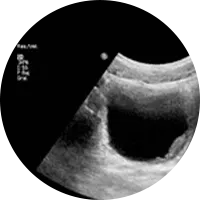

A Ecografia é um método de estudo e diagnóstico que permite, devido à emissão de ondas sonoras ou ultra-sons, examinar diversas áreas do corpo e órgãos e confirmar um diagnóstico clínico. Pode, portanto, ser usada para fins muito diversos como a observação ao pormenor do fígado, a vesícula biliar, rins, baço, tiróide, próstata, artérias e veias (Ecodoppler), entre outros. O exame de ecografia não causa nenhuma dor.

Existem vários tipos de preparação para os diferentes tipos de ecografia.